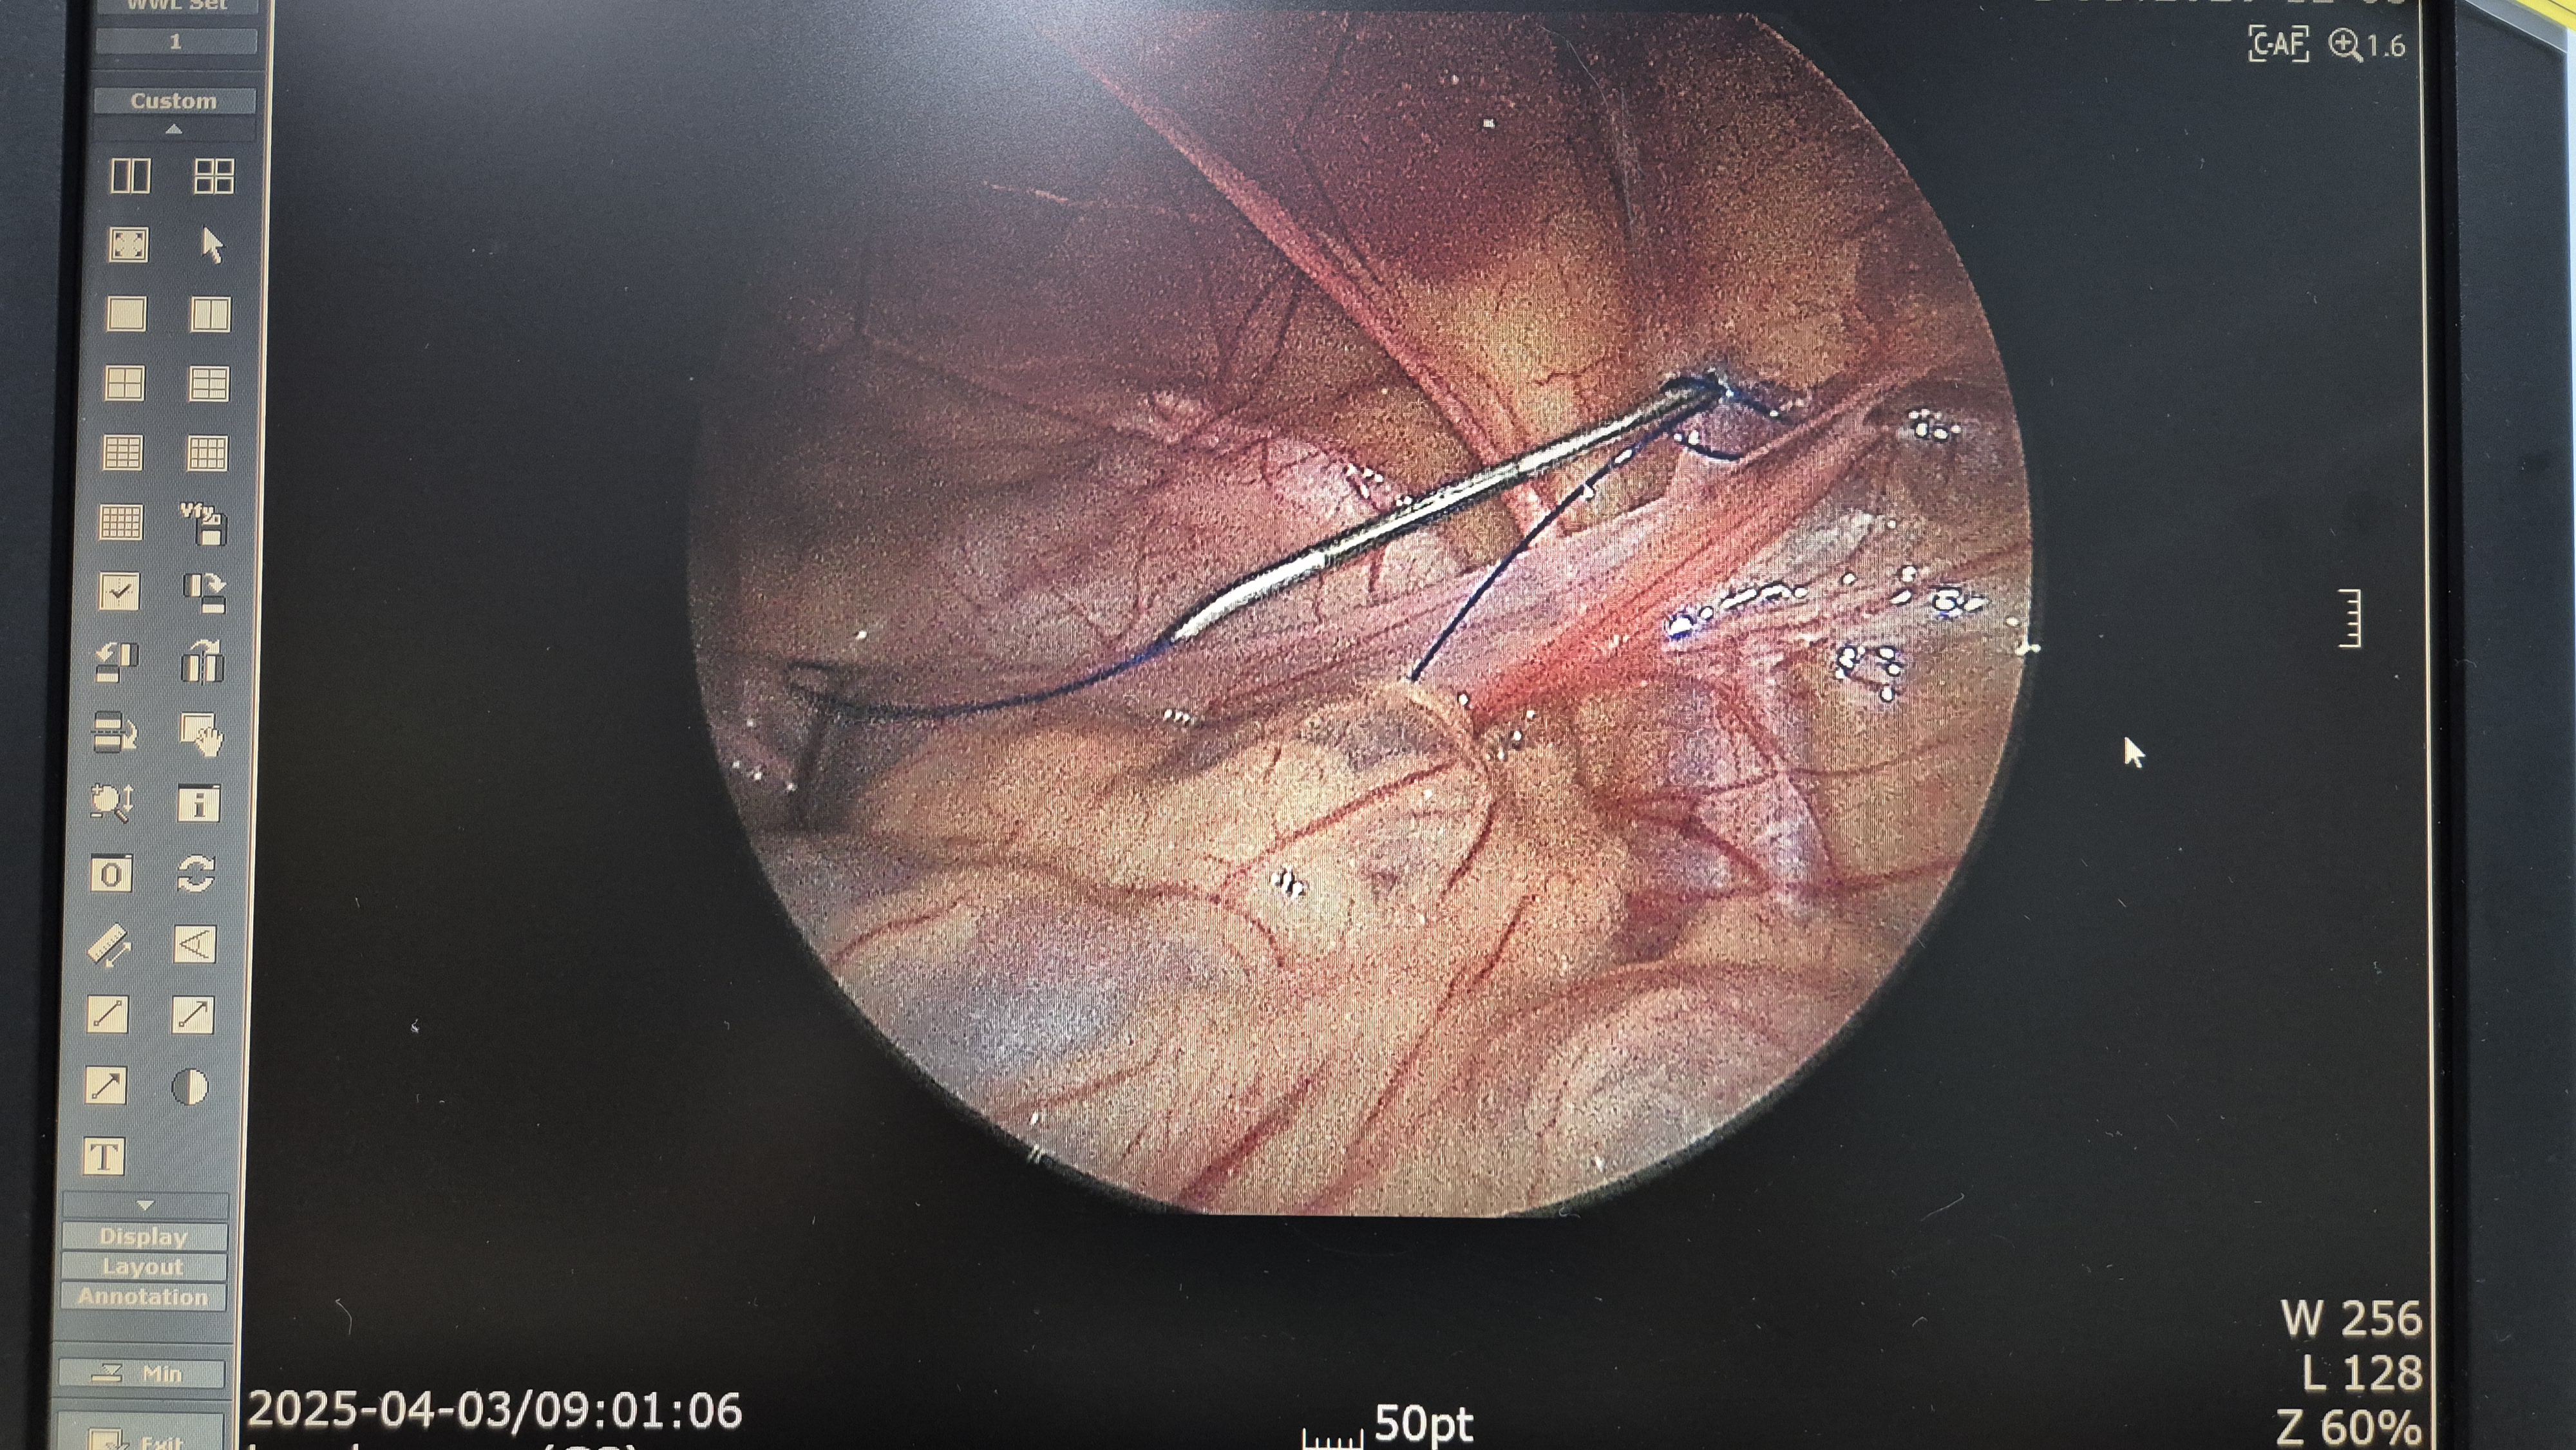

좌측 서혜부 탈장.

교정중.